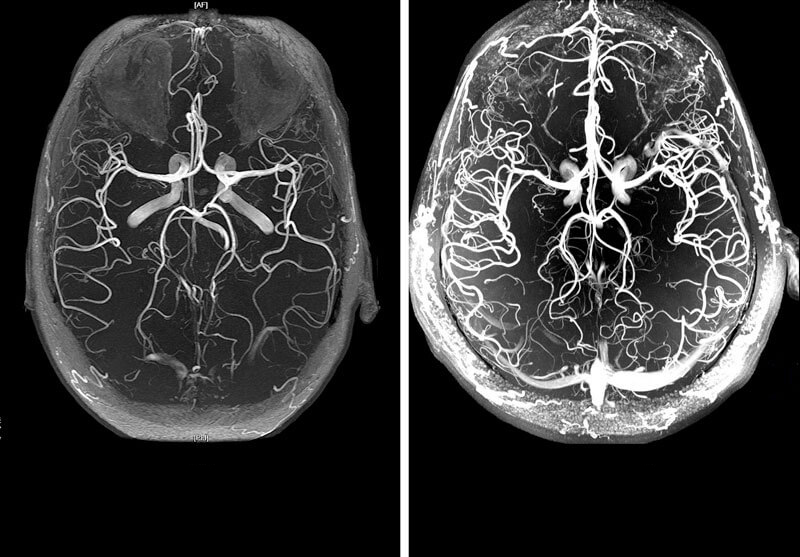

• Vasos sanguíneos del cerebro

El colesterol, que provoca la aterosclerosis de los vasos cerebrales, modifica tanto los vasos intracraneales como los extracraneales. La intensidad de los síntomas patológicos está directamente relacionada con el grado y la localización de las lesiones.

Además de la complicación más peligrosa, el ictus, puede haber depresión del SNC, desarrollo de trastornos mentales, pérdida de visión y deterioro de la memoria.

Brain stroke

Los síntomas iniciales de la lesión aparecen a partir de los 40-45 años.

En esta fase, pueden producirse "ataques isquémicos", acompañados de alteraciones sensoriales, trastornos del movimiento, anomalías de la visión, la audición y el habla. A pesar de la gravedad de los síntomas, son transitorios, reversibles y desaparecen por sí solos tras una única limpieza de los vasos sanguíneos con nutracéuticos.

El daño aterosclerótico grave puede provocar un accidente cerebrovascular, es decir, la necrosis del tejido cerebral. La sintomatología es la misma que en el caso anterior, pero no hay una mejora significativa después de la necrosis.

El cerebro también es responsable de la realización de las funciones mentales superiores. Por lo tanto, la formación de placas también conduce a una disminución de la inteligencia y la memoria y a cambios en el carácter (labilidad emocional, capricho, pereza). En ausencia de para limpiar los vasos sanguíneos de placas, esta lesión conduce al desarrollo de la demencia: la enfermedad de Alzheimer. Estas lesiones pueden provocar discapacidades o ser mortales.